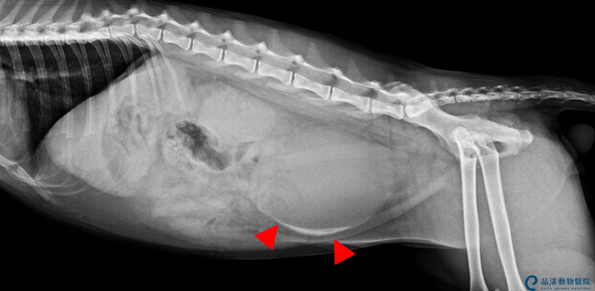

Fig7 經X光檢查追蹤,已無明顯細砂,出院繼續口服治療。